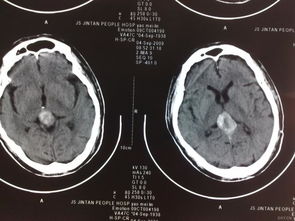

松果體位于丘腦的上后方,以柄附于第三腦室頂?shù)暮蟛浚瑸闄E圓形的小體,顏色淡紅,兒童時較發(fā)達(dá),一般七歲后逐漸萎縮,成年后不斷有鈣鹽沉著,??稍赬線片上見到。